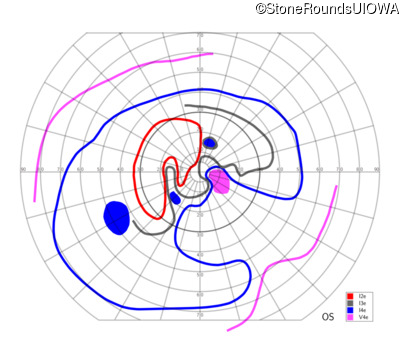

AR Stargardt Disease (IIA)

AR Stargardt Disease (IIA)

| Age at visit: 12 years |

| Age at visit: 13 years |

| Age at visit: 15 years |